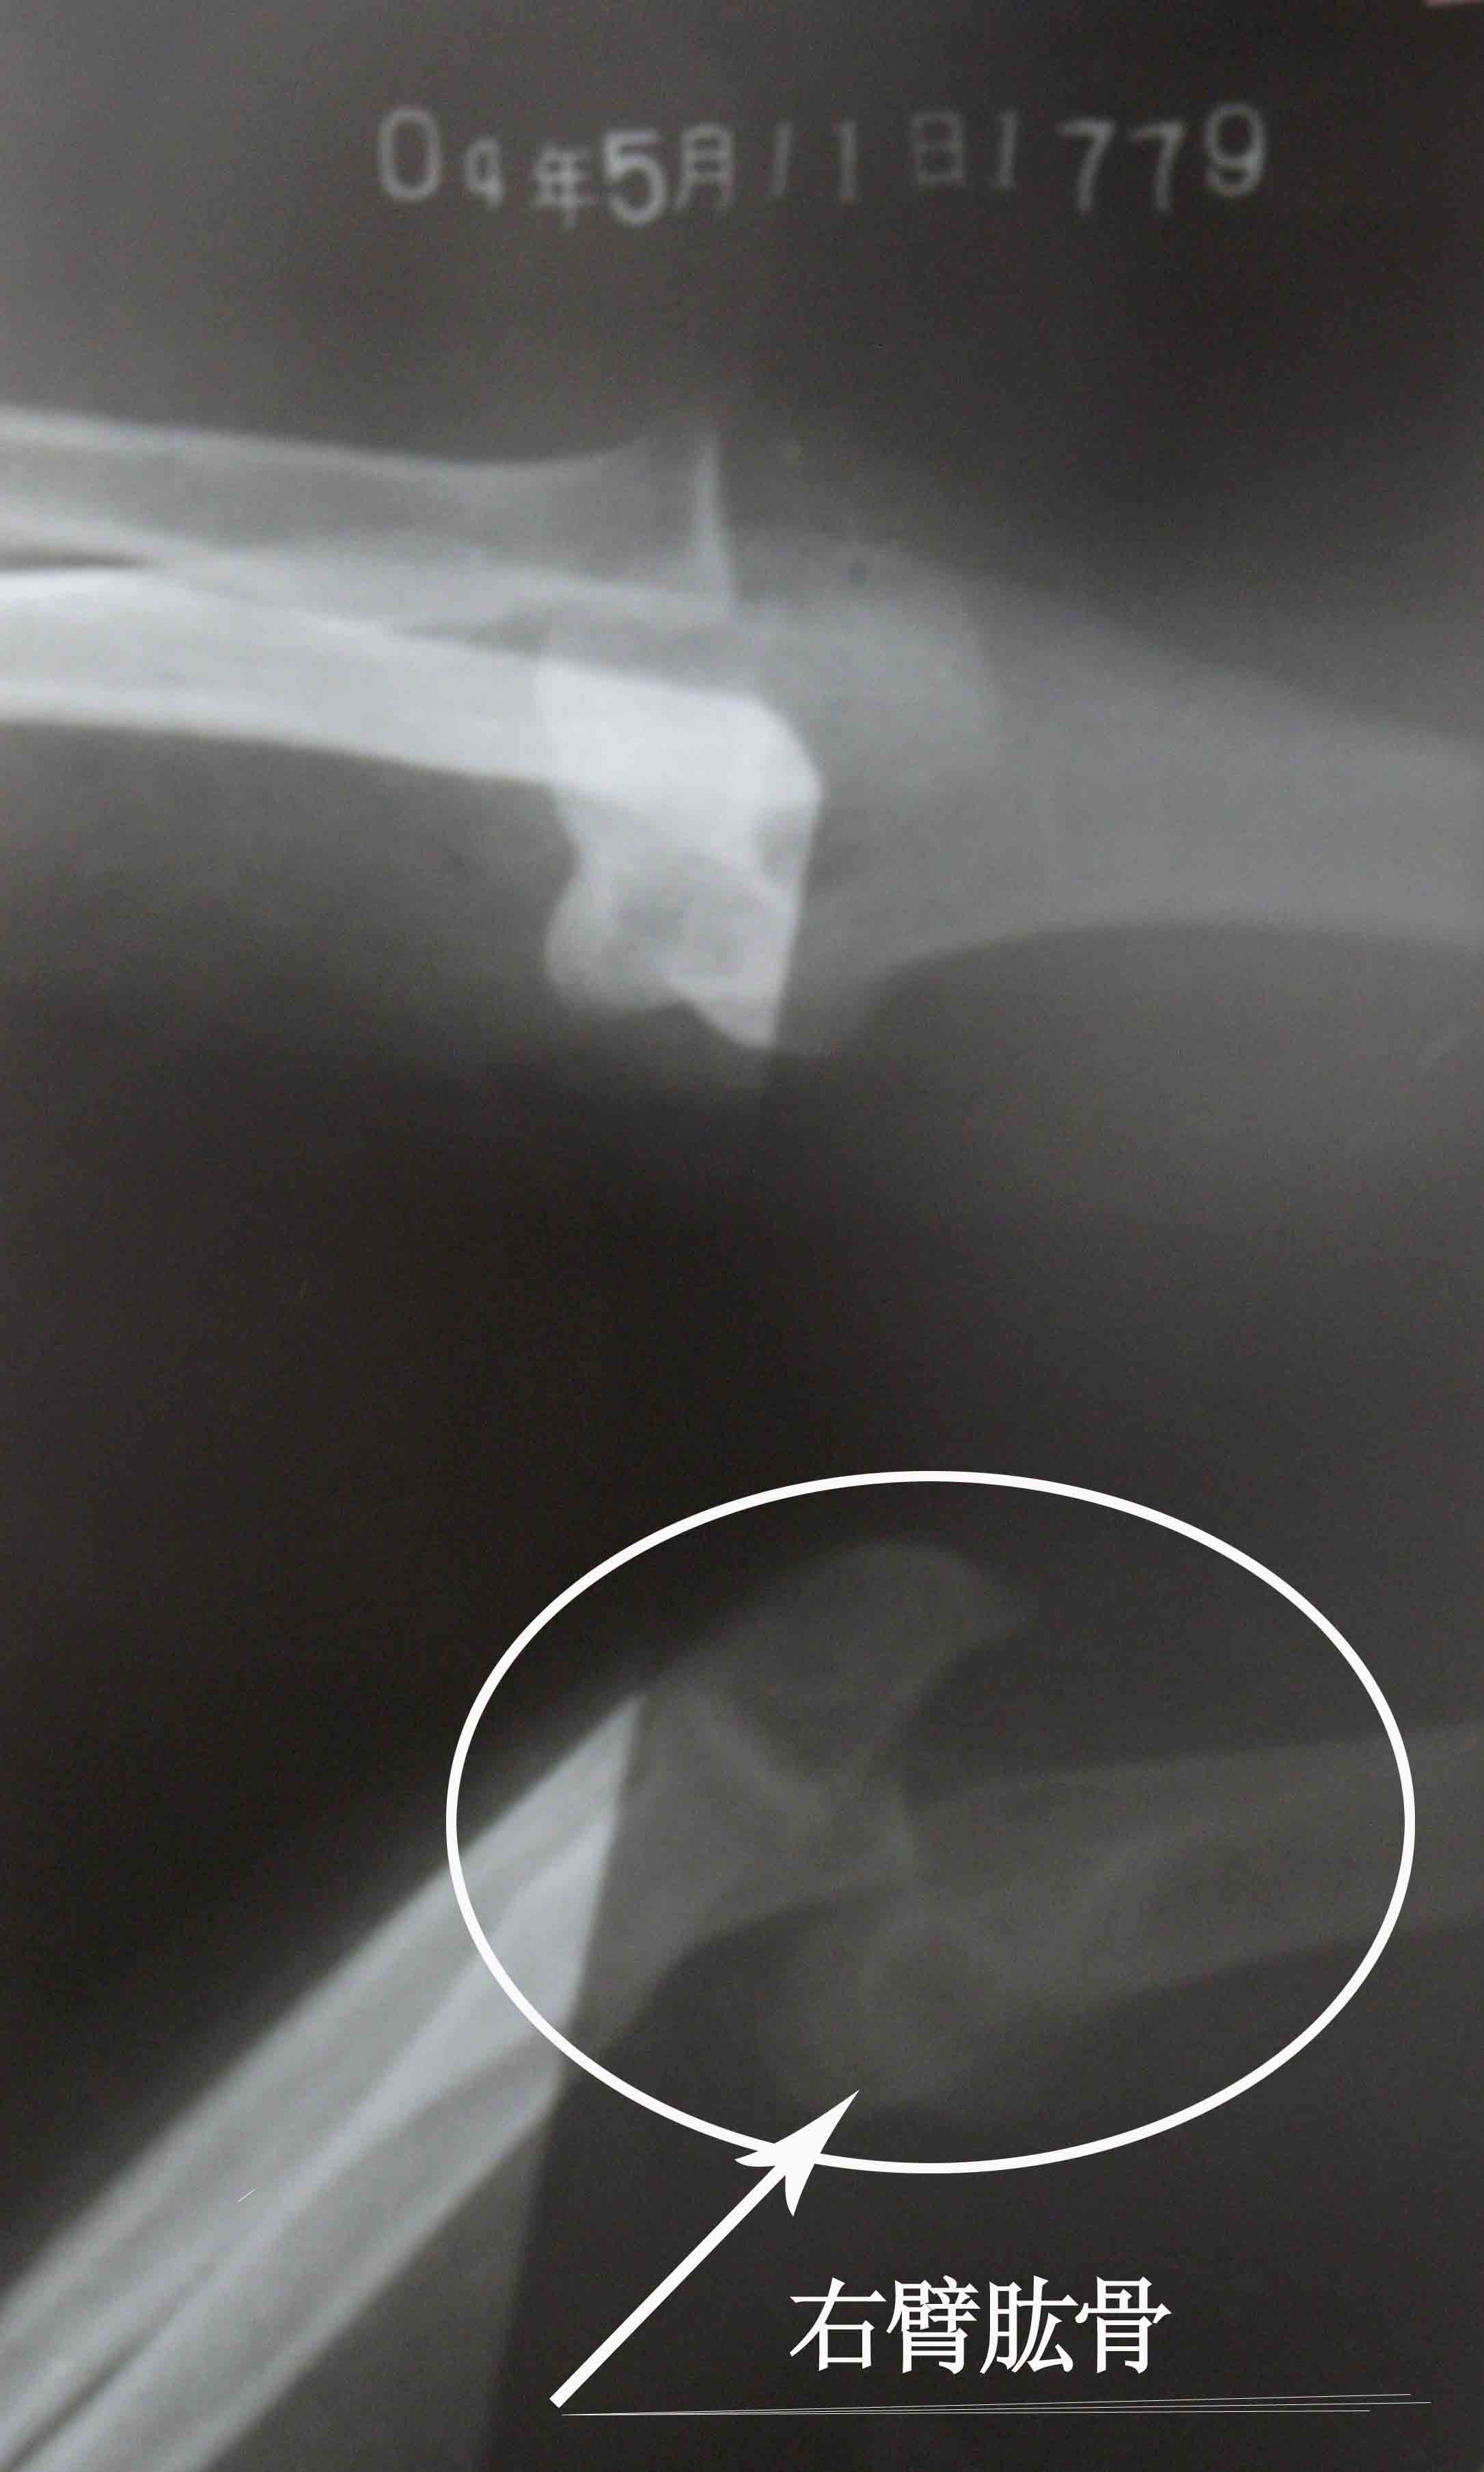

当天半夜我离开家以后,不断更换住处。三月二十九日那天,我刚把房门裂个缝,就见一个贼头贼脑的人正往我这里看,极度的恐惧顿时吓的我不知所措,只想快点离开住处,从窗往外看楼与地面并不高,我就跳了下来,结果受了伤,过路人把我抬到一辆出租车上,当司机知道我的遭遇时他什么都没说,把我送到了一个法轮功学员家。历经一个多月艰难的日子我终于能行走了,那段日子没有医疗(不敢住院怕被绑架),没有家人,只有痛苦和恐惧,若不是有大法的法理、同修的照顾真的很难走过来。后来到医院确诊我的右胳膊肘到手的那段骨头从胳膊肘里撞出来了,胸椎十二节和腰椎一节压缩性骨折,后来成为两椎体融合成一个椎体,当医生看到X光片子惊讶的说:“这是要瘫痪的!”当时腰椎骨折手术得十万余元,我被单位开除,没有生活来源,没钱医治。也只能在弟、妹的援助下做了胳膊的手术,术后胳膊再也不能直伸了,腰部连洗衣服都疼,更不能干重活,终生残疾。